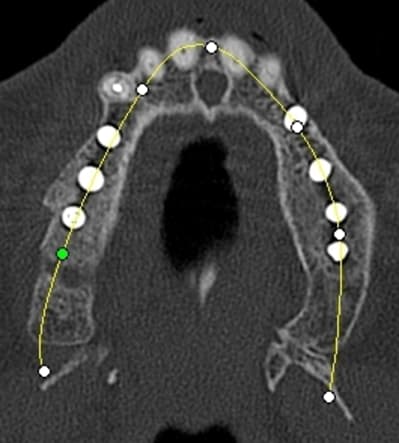

en ce qui concerne la planification j'ai une 3D kodak je me sert des cotes de l'implant Alphatech qui bien que n'ayant pas la même forme, a les mêmes dimensions.

pour votre plaisir mon ami 8 mois d'écarts

fenêtre fermée par du vitalos pas de membrane technique "grosse ouverture"

Gar cross section1 tgeo1t - Eugenol

Gar cross section2 aw0gxu - Eugenol

Garaxial1 az74ic - Eugenol

Gart axial2 veeu9c - Eugenol

Gart panoramic1 ssmlda - Eugenol

Gart panoramic2 isuhmz - Eugenol